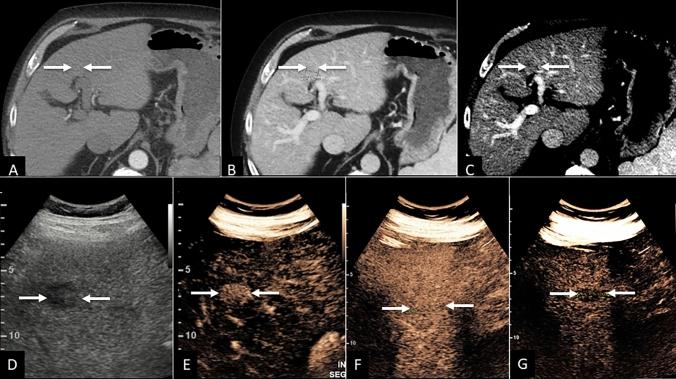

A prospective international multicenter validation study for CEUS Liver Imaging Reporting and Data System (LI-RADS) was conducted between January 2018 and August 2021. 646 patients at risk for HCC with focal liver lesions were enrolled. CEUS was performed using an intravenous ultrasound contrast agent within 4 weeks of CT/MRI. Liver nodules were categorized based on LI-RADS (LR) criteria. Histology or one-year follow-up CT/MRI imaging results were used as the reference standard. The diagnostic performance of CEUS was evaluated for inconclusive CT/MRI scan in two scenarios for which the AASLD recommends repeat imaging or imaging follow-up: observations deemed non-characterizable (LR-NC) or with indeterminate probability of malignancy (LR-3).

75 observations on CT or MRI were categorized as LR-3 (n = 54) or LR-NC (n = 21) CEUS recategorization of such observations into a different LR category (namely, into one among LR-1, LR-2, LR-5, LR-M, or LR-TIV) resulted in management recommendation changes in 33.3% (25/75) and in all but one (96.0%, 24/25) observation, the new management recommendations were correct.

CEUS LI-RADS resulted in management recommendations change in substantial number of liver observations with initial indeterminate CT/MRI characterization, identifying both non-malignant lesions and HCC, potentially accelerating the diagnostic process and alleviating the need for biopsy or follow-up imaging.